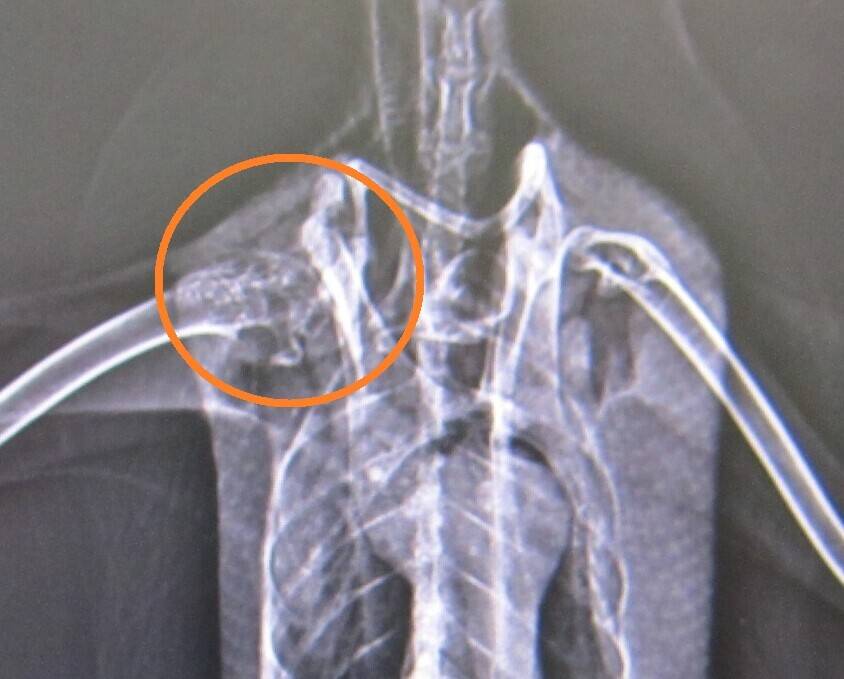

患部をアップにしてよ~く見てみると・・・

左右にズレがあるのがわかりますね。ここが患部です。